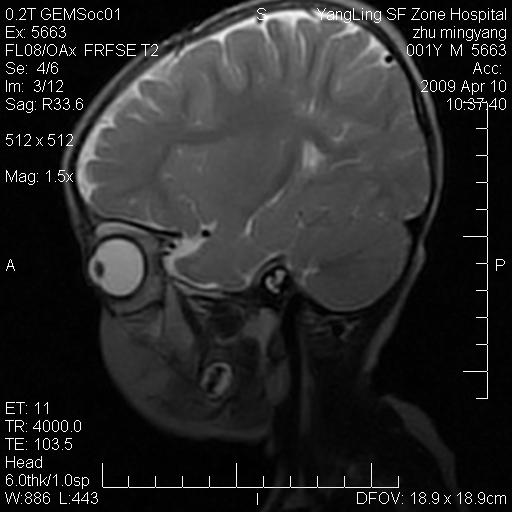

患者:1岁半,两天前外伤收住我院,ct检查小脑占位

考虑星形细胞瘤,建议增强

髓母细胞瘤或血管母细胞瘤,增强后可以鉴别;影像资料见 <。鱼博浪老师的《中枢神经系统ct与mr鉴别诊断》 小脑部肿瘤章节。

髓母细胞瘤或血管母细胞瘤!支持!

支持考虑髓母细胞瘤

考虑----髓母细胞瘤可能性大

考虑髓母细胞瘤或室管膜瘤。

支持髓母细胞瘤。

考虑髓母细胞瘤。

考虑髓母细胞瘤或星形细胞瘤

考虑髓母细胞瘤.

考虑髓母细胞瘤可能性大。

小脑肿瘤.考虑髓母细胞瘤可能.

就病灶部位及临床资料首先考虑髓母.